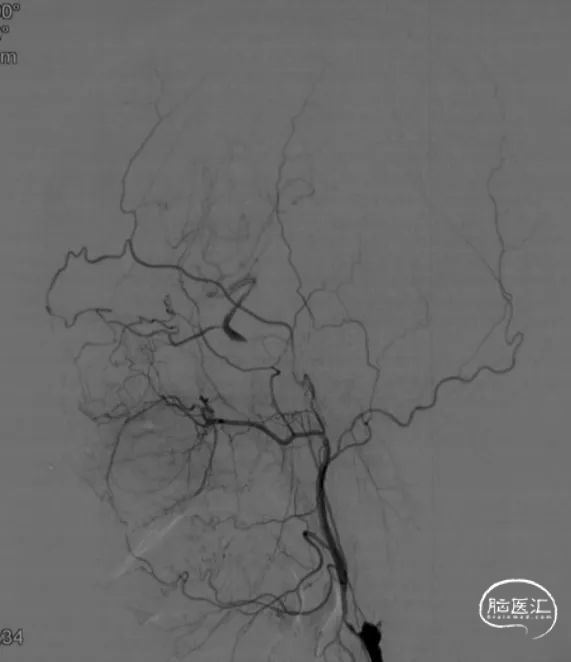

造影见右侧颈内动脉闭塞、颈内动脉开口可见残端,眼动脉向C6段代偿 Hasan分型为B型。

CAT7至C1-C2段多次负压抽吸,抽出大量血栓,C2段以远仍闭塞。

在清除近端血栓后,微导丝谨慎通过闭塞段

微导丝引导微导管超选至M1段,造影确认真腔

将Syphonet 4*30支架释远端放在M1段,建立远端保护

造影见Apollo支架内狭窄伴血栓形成

3*12 NC-trek支架内扩张

再次造影见M1段闭塞,C6段血栓影,考虑血栓向远端移位,但被支架捕获。

拟将抽吸导管越过Apollo支架至血栓近端,但多次尝试CAT7均无法通过支架。后予2/12 NC-trek球囊部分充盈,辅助CAT7通过Apollo支架到达C6段,抽拉结合,取出血栓,随后恢复前向血流。